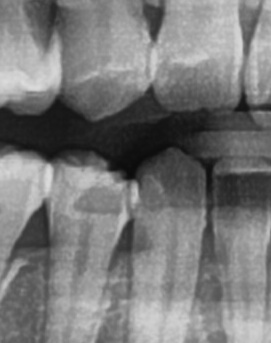

좀더 자세히 원인과 증상에 대해 살펴보면 어금니 뒤쪽은 치아 구조상 칫솔이 잘 닿지 않는 부위라서 음식물 찌꺼기가 남아 있거나 플라그가 쉽게 쌓이게 되는데 치아 사이 공간이 좁고 잇몸이 연약한 부분이라서 세균이 번식하기 쉬운 환경이 만들어지고, 이로 인해 잇몸이 붓거나 염증이 생길 가능성이 커질 수 있었어요

처음에는 가볍게 붓고 불편한 정도지만, 점점 심해지면 통증이 발생하거나, 잇몸이 붉어지고 단단해지면서 눌렀을 때 고름이 나오는 경우도 있어요. 이런 경우 단순한 염증이 아니라 치주염으로 발전할 가능성이 있기 때문에 치과에서 정확한 검진을 받는 것이 필요한 거예요

어금니 뒤 잇몸 부음의 문제는 사랑니가 원인이 되는 경우도 많은데 사랑니는 특히 현대인들의 경우 제대로 나오지 못하고 매복되는 경우가 많으며 완전히 나오지 않은 사랑니는 잇몸 속에서 자라면서 주변 잇몸을 자극할 수 있고, 일부만 노출되면 음식물이 끼면서 염증이 생기기도 하며 특히 어금니 뒤쪽 잇몸이 붓고 지속적으로 불편함을 느낀다면 사랑니로 인한 염증을 의심해 볼 수 있어요. 사랑니로 인한 문제의 경우 단순한 소염제나 구강 세정제로 해결되지 않고, 사랑니를 발치해야 잇몸 염증이 해결되는 경우가 많이 있어요

가장 주의해야 하는 문제 중에 치주염이 진행되면 어금니 뒤쪽뿐만 아니라 전체적인 잇몸이 약해질 수 있어요. 치주염은 치아를 둘러싸고 있는 조직이 손상되는 질환인데 특히 잇몸이 자주 붓거나 피가 나는 경우에는 치주염이 진행되고 있는 신호일 수 있기 때문에 단순한 잇몸 붓기로 넘기지 않는 것이 좋으며 치료를 받지 않으면 결국 치아를 지탱하는 뼈가 약해지고, 심한 경우에는 치아가 흔들리거나 빠질 수도 있었어요.